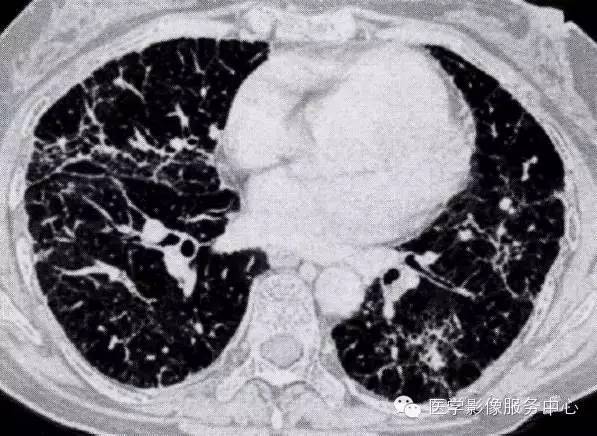

肺部炎症的"七大"常见ct表现

创伤性湿肺局限性实变影与结核反晕征鉴别诊断